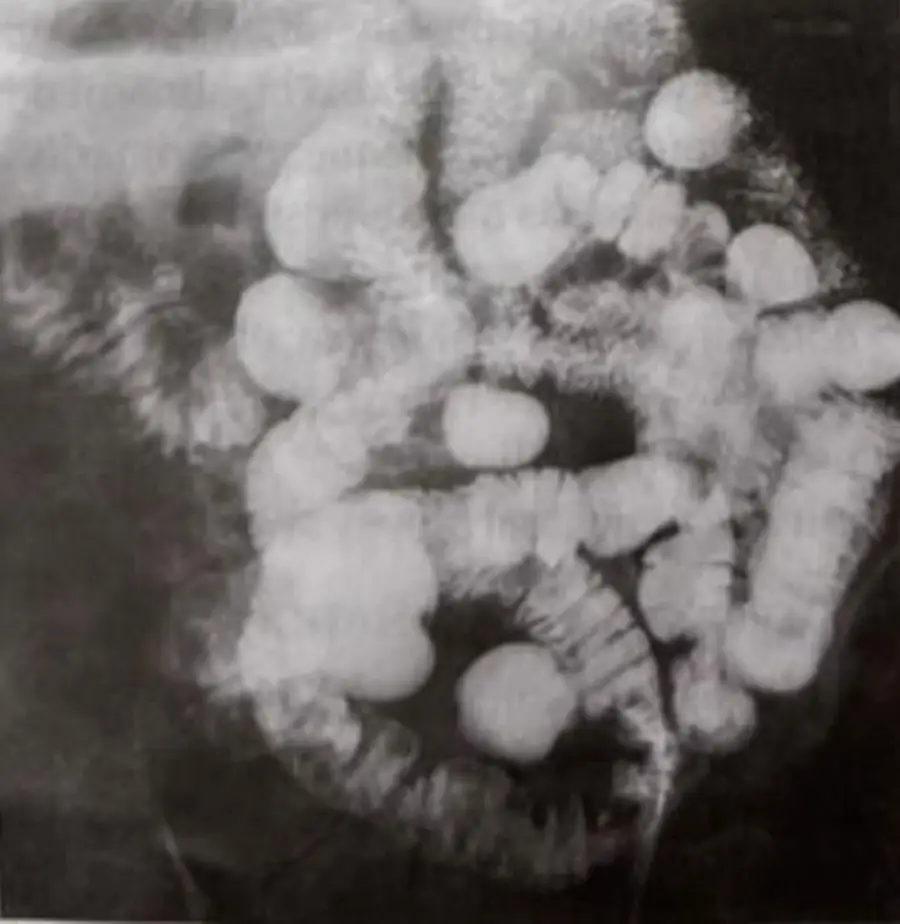

圖A:可見多發圓形或卵圓形填塞缺損,邊緣相對鈍圓,似偽息肉(pseudopolyps)或腸壁水腫之「拇指印(thumbprinting)」;流體分佈不均,缺乏典型的縱向裂隙或線狀潰瘍。

圖C:局部腸腔多處呈球狀或似燈籠狀小囊狀凸起,環繞於線狀裂隙之間,可疑為早期 cobblestoning(局部深縱橫潰瘍將黏膜隔離出正常島狀黏膜),但未見長段狹窄或傍脂硬結所致的「proud loop」。